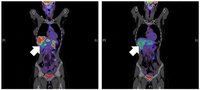

Phase-1-Studie mit Impfstoff VXM01 gegen Dickdarmkrebs Der für die Gefäßneubildung im Tumor wichtige Rezeptor (VEGFR-2) spielt eine entscheidende Rolle bei der Ausbreitung von Dickdarmkrebs. Ein